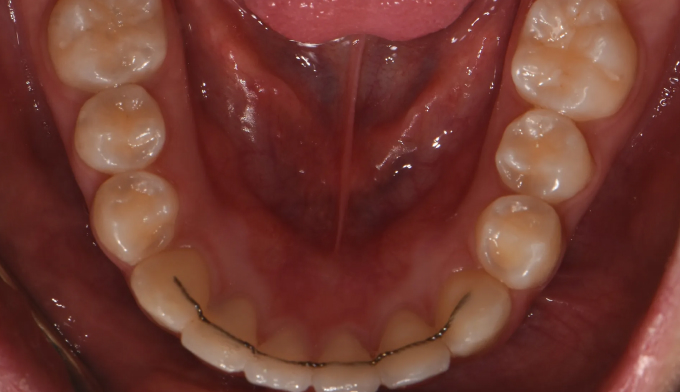

성장과정 중 어금니의 잘못된 맹출경로로 인해 쓰러지면서 나오는 경우가 종종 있습니다. 어금니가 쓰러지게 되면 해당부위에 음식이 저류되어 충치가 생기기 쉬워지며, 해당부위에 음식의 부패로 냄새와 함께 잇몸염증이 나타나기 쉽습니다. 나머지 부위에 대한 교정치료 욕구가 없다면 해당 어금니부위만 부분교정을 통해 어금니를 바로 세워줄 수 있습니다. 교정치료는 9개월 소요되었습니다.